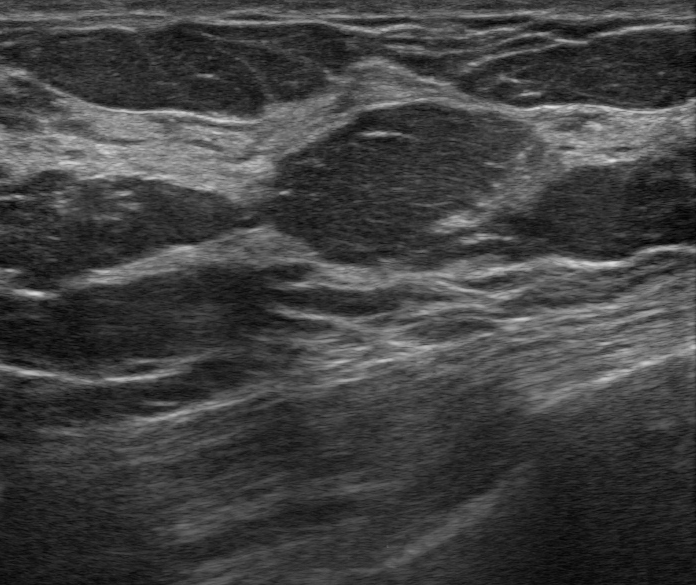

Imagen de masa mamaria